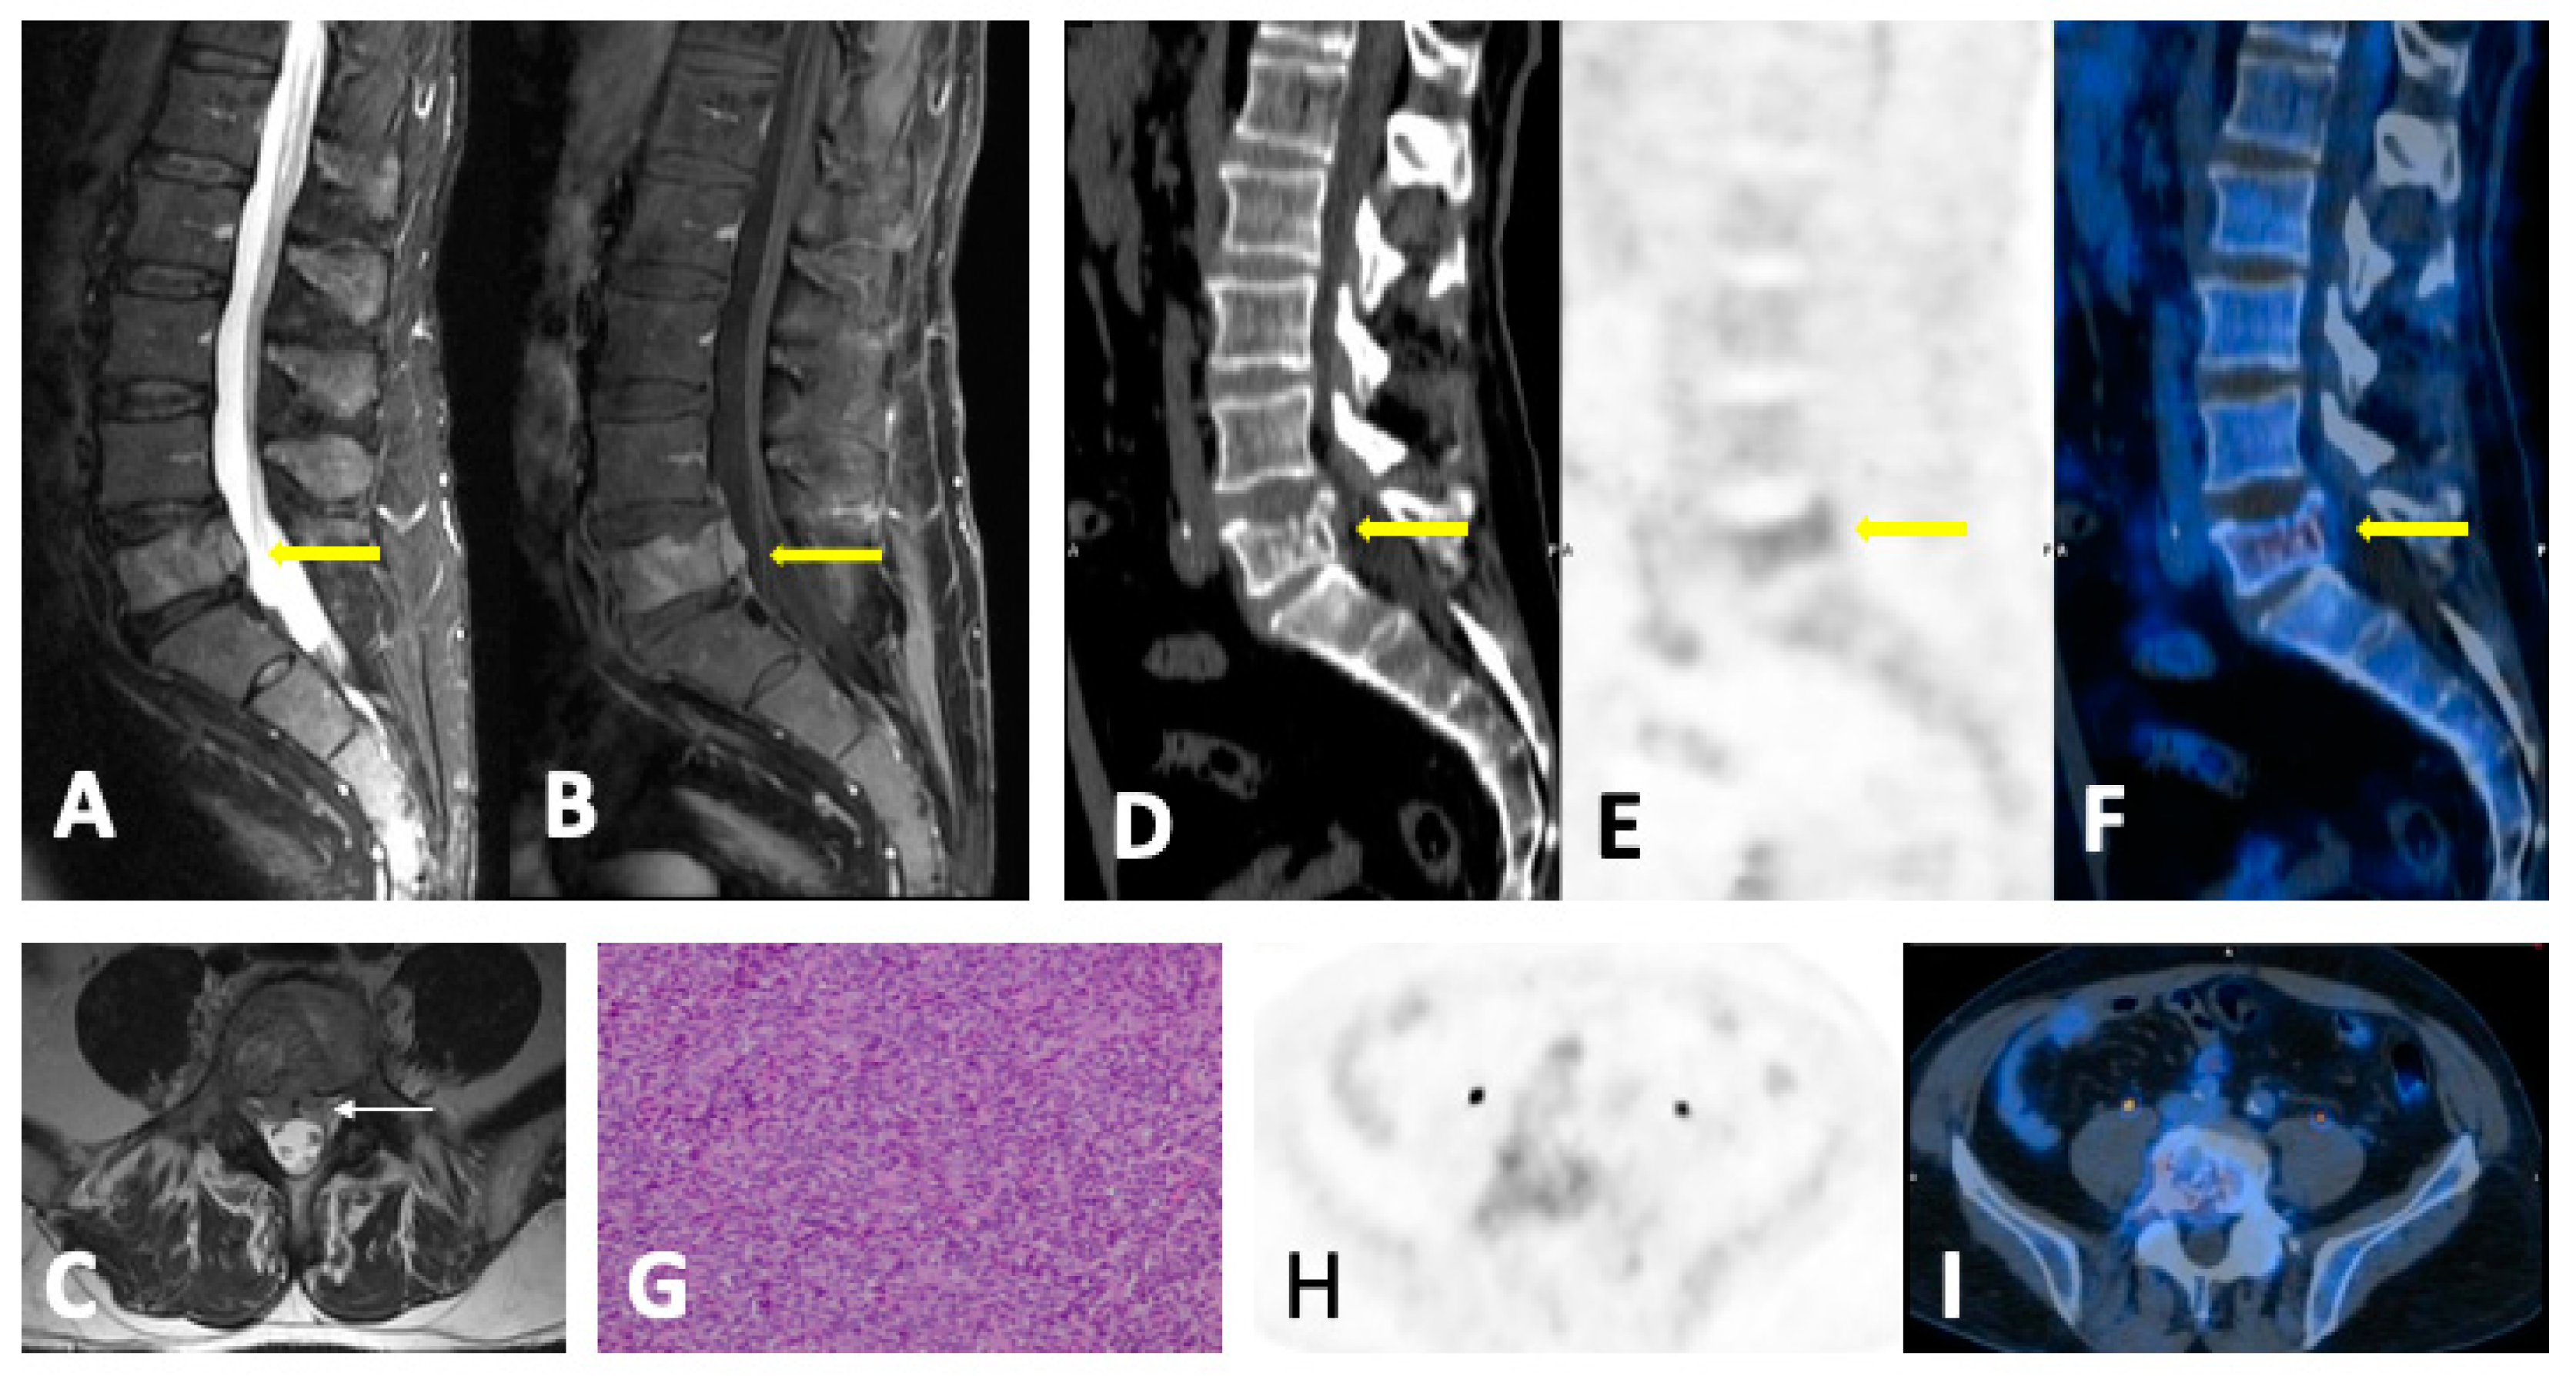

- Diffuse pattern: Diffuse disease can be suspected from a diffuse decreased signal on T1WI (either iso- or hypointense to intervertebral discs and muscle) and a diffuse increased signal throughout the marrow on T2FSWI, STIR, or high b-value DWI. Marrow ADC values above 600–700 μm2/s in a nontreated and newly diagnosed patient with MM could be used to increase confidence for the diagnosis of diffuse marrow involvement [33] (Figure 7). Due to potential false-positive findings, diffuse disease in imaging must be supported by bone marrow trephine biopsy [26].

4.3. Follow-Up Imaging Features